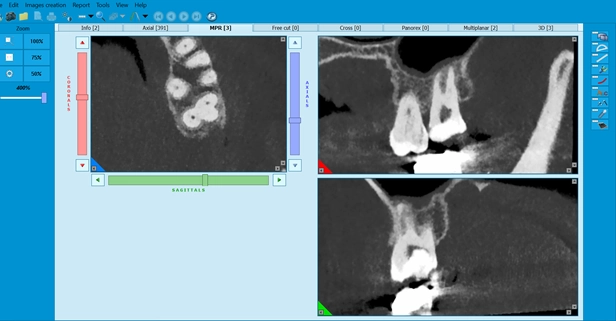

۳. نقش رادیوگرافی و CBCT

رادیوگرافی معمولی (Periapical X-ray): ابزار اصلی و اولیه است ولی دو بعدی بودن آن محدودیت دارد.

CBCT:

o تشخیص ضایعات اپیکال کوچک یا مخفی

o بررسی شکستگی‌های عمودی ریشه

o شناسایی ریشه‌های اضافی و کانال‌های غیرمعمول

o کمک به برنامه‌ریزی در درمان‌های مجدد و جراحی اندودنتیک

مطالعات نشان داده‌اند که CBCT نسبت به رادیوگرافی معمولی حساسیت بالاتری در شناسایی ضایعات آپیکال دارد (Patel et al., IEJ 2009).

معاینه دقیق کلینیکی + رادیوگرافی + در صورت نیاز CBCT برای افتراق ضروری است.

• CBCT برای تعیین مسیر کانال قبل از شروع